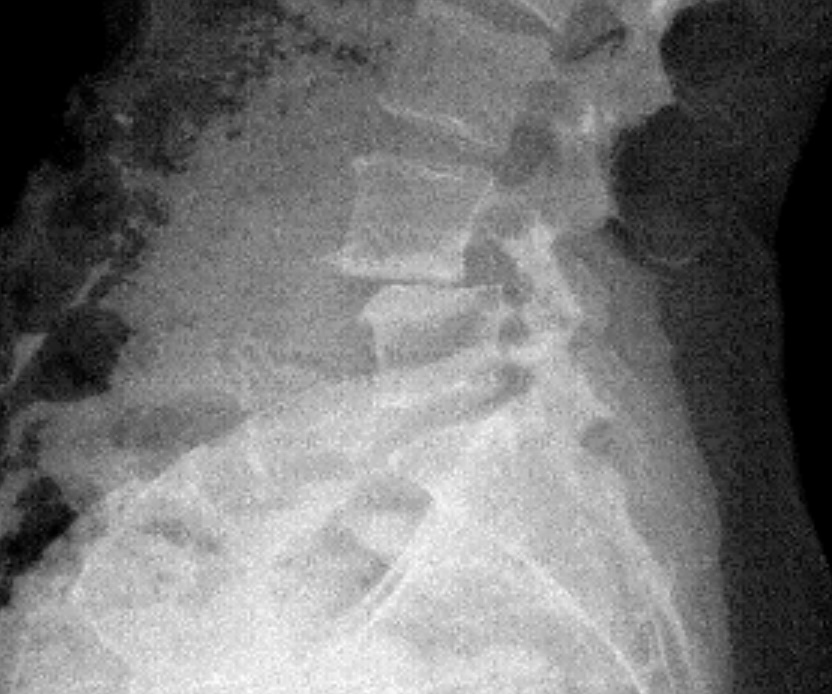

Spinal Stenosis

I’ve always been active. I’ve done everything - boxing, Pilates, barre, and in my mid-40s after Covid I started to run and ran two half marathons in 2022 and 2023. I first started to experience pain in my hip and down my right leg during my first pregnancy. The leg pain subsided but the hip pain never did. When I took up running, that’s when things went downhill. First the plantar fasciitis, then the constant leg pain like I had pulled a hamstring. Dr. Baxi at first used cortisone on both my foot and back. Then we did shockwave therapy on my foot which helped tremendously. But after a second epidural on my back didn’t work I knew it was time for surgery. Dr. Dowdell was great. It was tough at first and he assured me after six months I could get back to my former life. Now I’m back to boxing and I’m hoping to start training for and run in the NYC marathon this Fall.